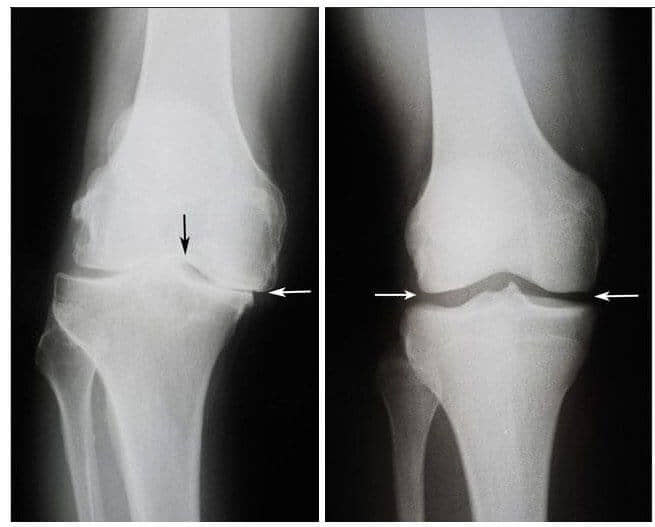

Ve sonra mucize gerçekleşti. Bu doktor her gün Vuslat Hanım’ın evine gelmeye başladı ve bu şifalı kremle ona masaj yaptı. Dört hafta sonra tekerlekli sandalyesinden kalkıp doktora kendi başına yürüyebildi. Altı hafta sonra, Vuslat Menekşe’nin eklemleri osteoartritten tamamen kurtuldu. Çekilen röntgen bunu doğruladı.

Solda: Vuslat Menekşe’nin (75) sağ diz eklem röntgeni. Kıkırdak

dokusu neredeyse tamamen yok oldu. Doktorların tavsiyesi eklemin yapay bir eklemle

değiştirilmesidir.

Sağda: JointFlex tedavisinden sonra Vuslat Menekşe’nin sağ diz eklem röntgeni.